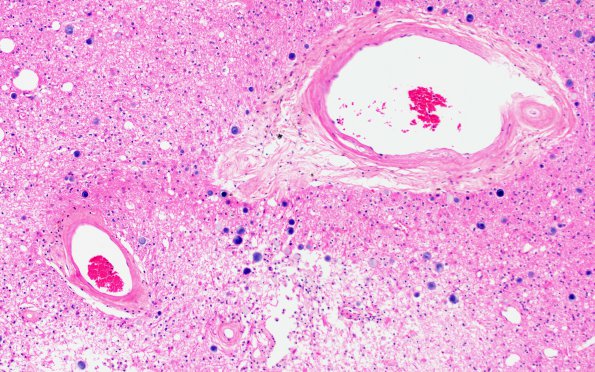

Washington University Experience | VASCULAR | Subcortical Arteriosclerotic Encephalopathy | 1B1B Binswanger's Dz (Case 1) R36 H&E 20X 1

1B1B,C Arteriosclerotic thickened vessels of multiple sizes are involved adjacent to (1B1B) or within cystic infarcts (1B1C) (H&E)